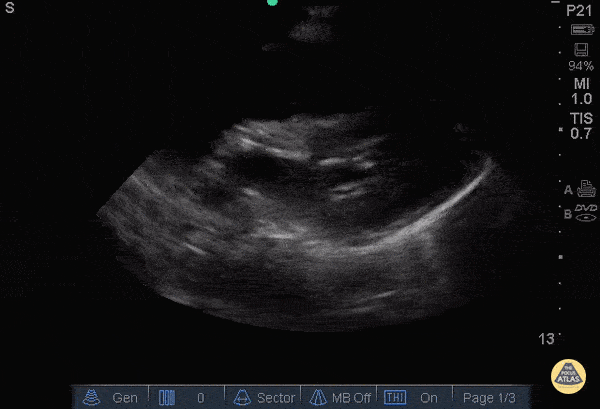

Elderly F w/ PMHx HTN and metastatic cancer arrived as a notification for sudden, witnessed syncope. EMS found PEA on EKG, intubated her, delivered 1 shock by AED, and obtained ROSC after 2 rounds of Epi. During transport she became pulseless again, and a 2nd ROSC was achieved w/ Epi in ED. During pulse check echo was used to evaluate for organized cardiac activity. Echo revealed a mild pericardial effusion w/o tamponade in PLAX, normal cardiac architecture, and absence of organized atrial and ventricular contractions. Disorganized ventricular movement correlated w/ VFib on the monitor. Rescuer pulse palpation is only 78% accurate according to Tibballs and Russell (2008). POCUS in cardiac arrest allows for the assessment of organized cardiac activity w/o a palpable pulse, and for further evaluation of the Hs and Ts in PEA arrest. Given the need to maintain coronary perfusion w/ high quality CPR, the PLAX view is typically the fastest, provides actionable information and can be performed during standard ACLS pulse checks. Tibballs J, Russell P. "Reliability of pulse palpation by healthcare personnel to diagnose paediatric cardiac arrest." Resuscitation 2008; 78: 135-40. Submitted by Paul Pukurdpol, MD @PaulyPocket